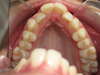

AVANT